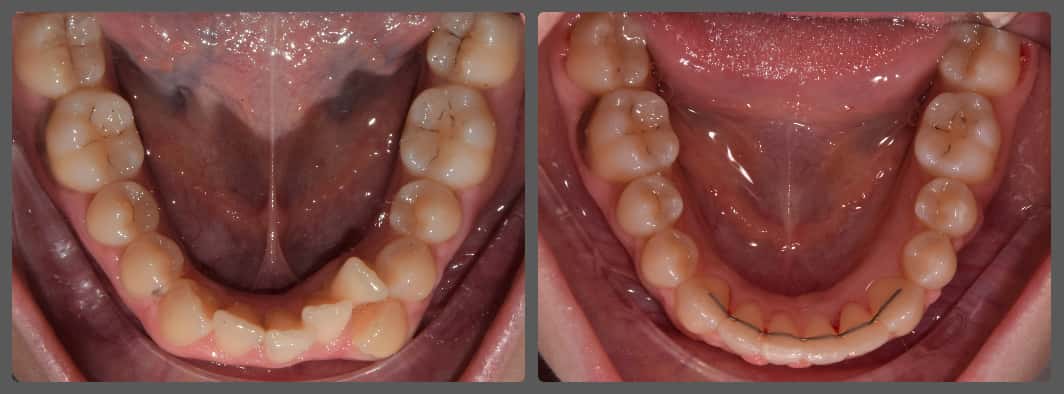

Zoli torlódott alsó fogai miatt szeretett volna fogszabályozó készüléket. Régebben 2 db felső kisőrlő fog eltávolításával már fogszabályozták, azonban az alsó fogív eltérései jelentősek voltak. A torlódás mellé közepes mértékű mélyharapás társult, valamint a bal oldali kisőrlő fogaknál non-occlusiot figyeltem meg. Ez azt jelenti, hogy esetünkben a felső első kisőrlő fog az alsó első és második kisőrlő fog közé, de azok külső felszínére harap. Ez a felső fogat kifelé, az alsókat befelé, a nyelv felé dönti és hosszútávon súlyos elváltozást okoz. Alsó-felső Pitts21 rögzített fogszabályzóval, intermaxilláris gumihúzással, harapásemelőkkel és tolórugókkal Zoli fogait nagyon gyorsan, 13 hónap alatt sikerült tökéletes pozícióba szabályoznunk, mind esztétikai, mind funkcionális szempontból (persze ehhez kellett a töretlen lelkesedése, együttműködése is). A kezelés végén az alsó fogívre fix retainert helyeztem fel az elért állapot megőrzésére. A végeredmény úgy gondolom mindent elmond!